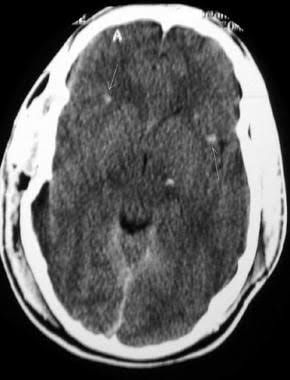

These symptoms most commonly include a headache. The other post-concussive symptoms can include dizziness, nausea, vomiting, and fatigue. However, patients with a severe diffuse axonal injury may also present with a loss of consciousness and remain in a persistent vegetative state.